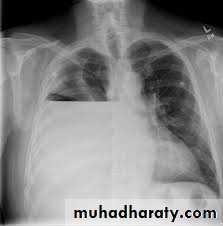

Differential Diagnosis for upper Abdominal Pain and Tenderness

Perforated Viscus, especially peptic ulcer

Erect CXR

Pneumonia

CXR